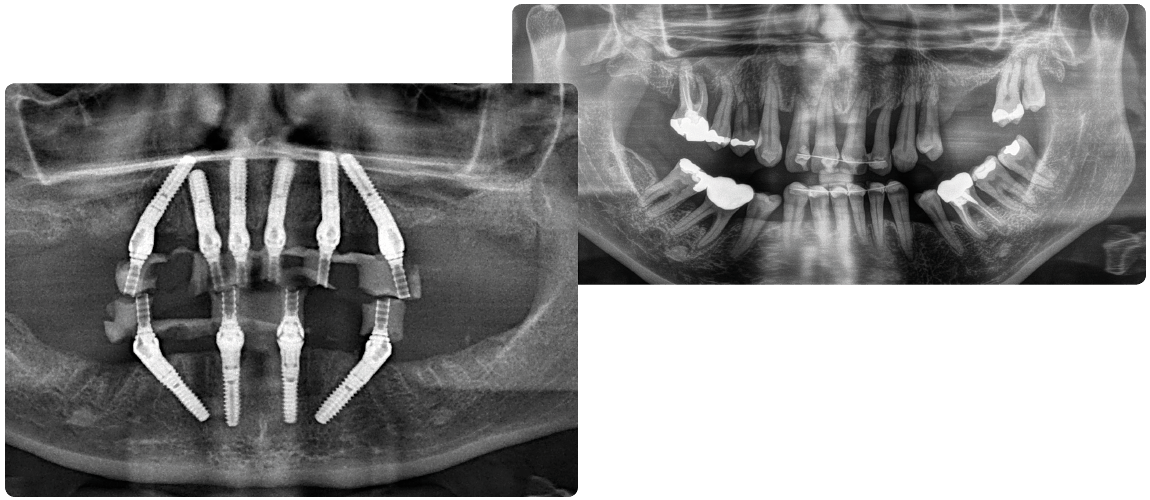

FAST & FIXED İmplant Yöntemi (All on Four)

Fast & Fixed implant tekniği, tam dişsiz hastalarda belirlenen açılara göre yerleştirilen ; dört adet dental implant üzerine diş protezinin sabitlenmesini sağlayan bir yöntemdir.

Tam dişsiz hastalara aynı gün, tek bir cerrahi işlem ile geçici veya daimi sabit diş protezi yapılabilme imkânı sunar.

Gerekli görüldüğünde implant sayısı 5 veya 6’ya çıkarılabilir.